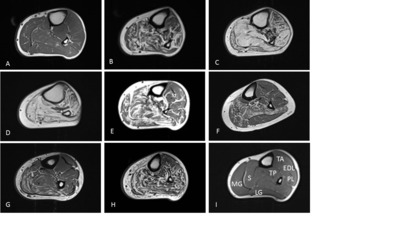

PURPOSE OF REVIEW: Charcot-Marie-Tooth disease (CMT) is one of the commonest inherited neuromuscular diseases with a population prevalence of 1 in 2500. This review will cover recent advances in the genetics and pathomechanisms of CMT and how these are leading to the development of rational therapies. RECENT FINDINGS: Pathomechanistic and therapeutic target advances in CMT include the identification of the ErbB receptor signalling pathway as a therapeutic target in CMT1A and pharmacological modification of the unfolded protein response in CMT1B. In CMT2D, due to mutations in glycyl-tRNA synthetase, vascular endothelial growth factor-mediated stimulation of the Nrp1 receptor has been identified as a therapeutic target. Preclinical advances have been accompanied by the publication of large natural history cohorts and the identification of a sensitive biomarker of disease (muscle MRI) that is able to detect disease progression in CMT1A over 1 year. SUMMARY: Advances in next-generation sequencing technology, cell biology and animal models of CMT are paving the way for rational treatments. The combination of robust natural history data and the identification of sensitive biomarkers mean that we are now entering an exciting therapeutic era in the field of the genetic neuropathies.